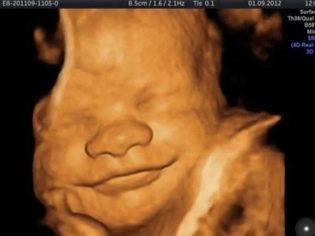

По согласованию с диагностом на второе УЗИ можно взять с собой и отца будущего ребенка. На мониторе сканера его ждет нечто довольно интересное, ведь теперь плод хорошо виден, можно полюбоваться его профилем, увидеть ручки и ножки, пальчики, нос, рот, глазницы, половые органы. Если УЗИ делается в 3D-формате, то будущие родители даже смогут увидеть, на кого больше похож карапуз.

Как выглядит ребенок на 33 неделе в 4D смотрите видео:

Трехмерное и четырехмерное УЗИ делают дольше (40–60 мин). Зато будущая мама получает возможность посмотреть настоящий цветной фильм о своем малыше.